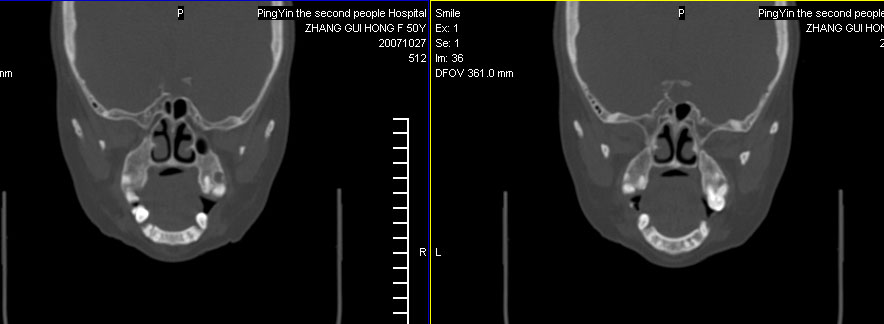

标题: CT10219:蝶鞍区有无异常?

女。50岁.头疼恶心半月余.双上颌窦区压疼明显,曾有高血压.现基本控制.

有问题,双侧侧脑室扩大,感觉鞍区有肿块,建议增强扫描.

感觉鞍区异常,建议增强扫描.